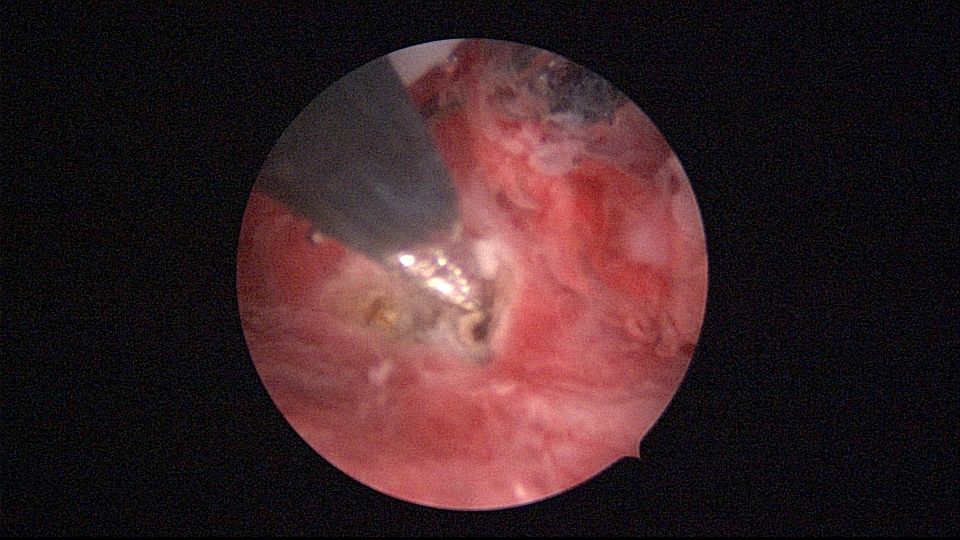

患者40岁,G0P0,原发不孕10+年,20+岁严重痛经,多家医院行腹腔镜手术治疗腺肌症合并多发性肌瘤,宫腔镜切除内膜息肉,前后肌注GnRH-a6针,痛经明显缓解。2017年试管助孕一次,失败,放弃生育需求,现要求放置曼月乐环并固定。2024年5月行宫腔镜下曼月乐不锈钢挂钩固定,子宫前位,宫深7cm,宫腔形态正常,宫内膜正常,双侧输卵管开口可见,将曼月乐环用4号丝线与挂钩连接并固定于宫底(第一次做宫腔镜下节育环固定,没有想到利用曼月乐尾丝连接环)。2024年6月复查B超,曼月乐固定装置扎入宫底肌层0.46cm,环位置正常,2025年5月复查B超,曼月乐顶端距宫底1.5cm。